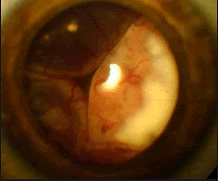

患儿,男性,2岁,足月顺产,无吸氧史。家长发现右眼白瞳症,对光线反应不敏感。超声波提示眼内占位性病变,直径约6mm。无全身性疾病,无眼病家族史。

可能是哪一种疾病(如图)()

-

辅助检查中最有意义的发现是(如图)()

哪一种治疗为最佳选择()